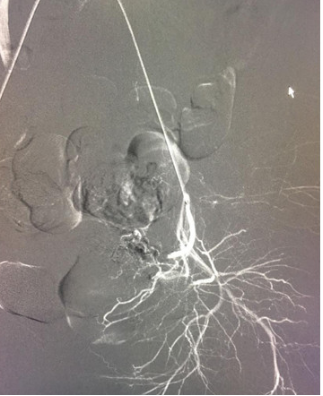

该患者孕囊位于子宫切口处肌壁内,且该处肌层菲薄,厚约3.75px(如图1,2,3)。出血风险及子宫穿孔风险极大。为了保留生育功能,确保患者生命安全,我院妇科积极发起多学科联合诊疗(MDT)会议,特邀请放射科、麻醉科、超声科等相关科室开展讨论,一致决定先由放射科行子宫动脉栓塞术并灌注甲氨蝶呤杀胚治疗(微创介入),72小时之内再行清宫术。最终,该患者在放射科顺利完成甲氨蝶呤灌注和双侧子宫动脉栓塞(如图4-5)的情况下,第二天由妇科在超声科床旁监护下成功完成清宫术(如图6),宫腔镜检查宫腔及切口处无异常。术中出血仅有5ml(出血量较常规清宫术明显减少),并于术后第三天康复出院。

图4:子宫动脉造影,血管迂曲,血供丰富,染色深浓。

值得了解

子宫动脉栓塞术:是通过介入方法用栓塞物(如明胶海绵)将子宫动脉栓塞,以达到快速止血的作用。主要用于子宫急性大量出血时可行急诊栓塞,也用于异位妊娠出血,瘢痕子宫胎盘植入清宫术前预防出血。它作为一个有效的止血微创手术,为产科止血又提供了一个有效手段;它作为一种血管介入手术,无需开刀,损伤小,通过股动脉穿刺,超选择性插管术,将造影导管超选进入子宫动脉(如图4),再用明胶海绵栓塞子宫动脉以达到止血作用(如图5)。